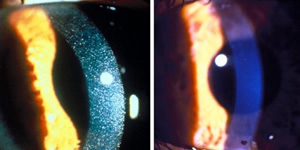

Cystinosis affects approximately 600 children and young adults in the United States and 2,000 individuals worldwide. It is a rare, genetic lysosomal storage disease, characterized by the abnormal accumulation of the amino acid, cystine. The disease causes cystine crystals to build up in various organs of the body, including the corneas, kidneys, liver, pancreas, muscles, brain and white blood cells. Corneal cystine accumulation can lead to eye complications such as squinting, foreign body sensations, changes in visual acuity, corneal haziness and sensitivity to light. Other complications of cystinosis include rickets, growth failure, muscle wasting, diabetes, hypothyroidism and difficulty swallowing.

However, cysteamine in pill form cannot reach the cornea to prevent irritating and vision-threatening symptoms. An eye-drop solution met the unique need for treating eyes and an NEI study commenced in 1986. In 1995, Sigma-Tau Pharmaceuticals, Inc. began manufacturing the eye-drop solution, trademarked Cystaranâ„¢, under an orphan drug provision from the FDA. Pharmaceutical products developed specifically for a rare condition may receive this designation. This drug now is the only FDA-approved, ophthalmic treatment for cystinosis.

The clinical safety and efficacy of the ophthalmic therapy were previously evaluated in controlled clinical trials conducted by NIH in approximately 250 patients. Results of these studies support the use of ophthalmic cysteamine as an effective treatment for corneal cystine crystals. "Cysteamine treatment has dramatically changed the course of this disease," said Dr. Gahl. "The approval of oral and topical [eyedrop] formulations of the drug is a homerun for cystinosis patients."

For the past 26 years, cystinosis patients enrolled in an NEI clinical study have travelled to the NIH Clinical Center about once a year, where doctors have administered the eye drops and recorded successful results. "We know the drops work, and that lots of people benefit significantly from using them," said Rachel Bishop, M.D., M.P.H., chief of NEI's Consult Service Section and current principal investigator for the treatment trial. "This is a major development, because there are no other approved ophthalmic treatments for cystinosis. For the first time, patients all over the country will now have access to treatment."

For a picture of one patient's corneas, before and after treatment, go to www.genome.gov/dmd/img.cfm?node=Photos/Technology/Medical%20Conditions&id=79209